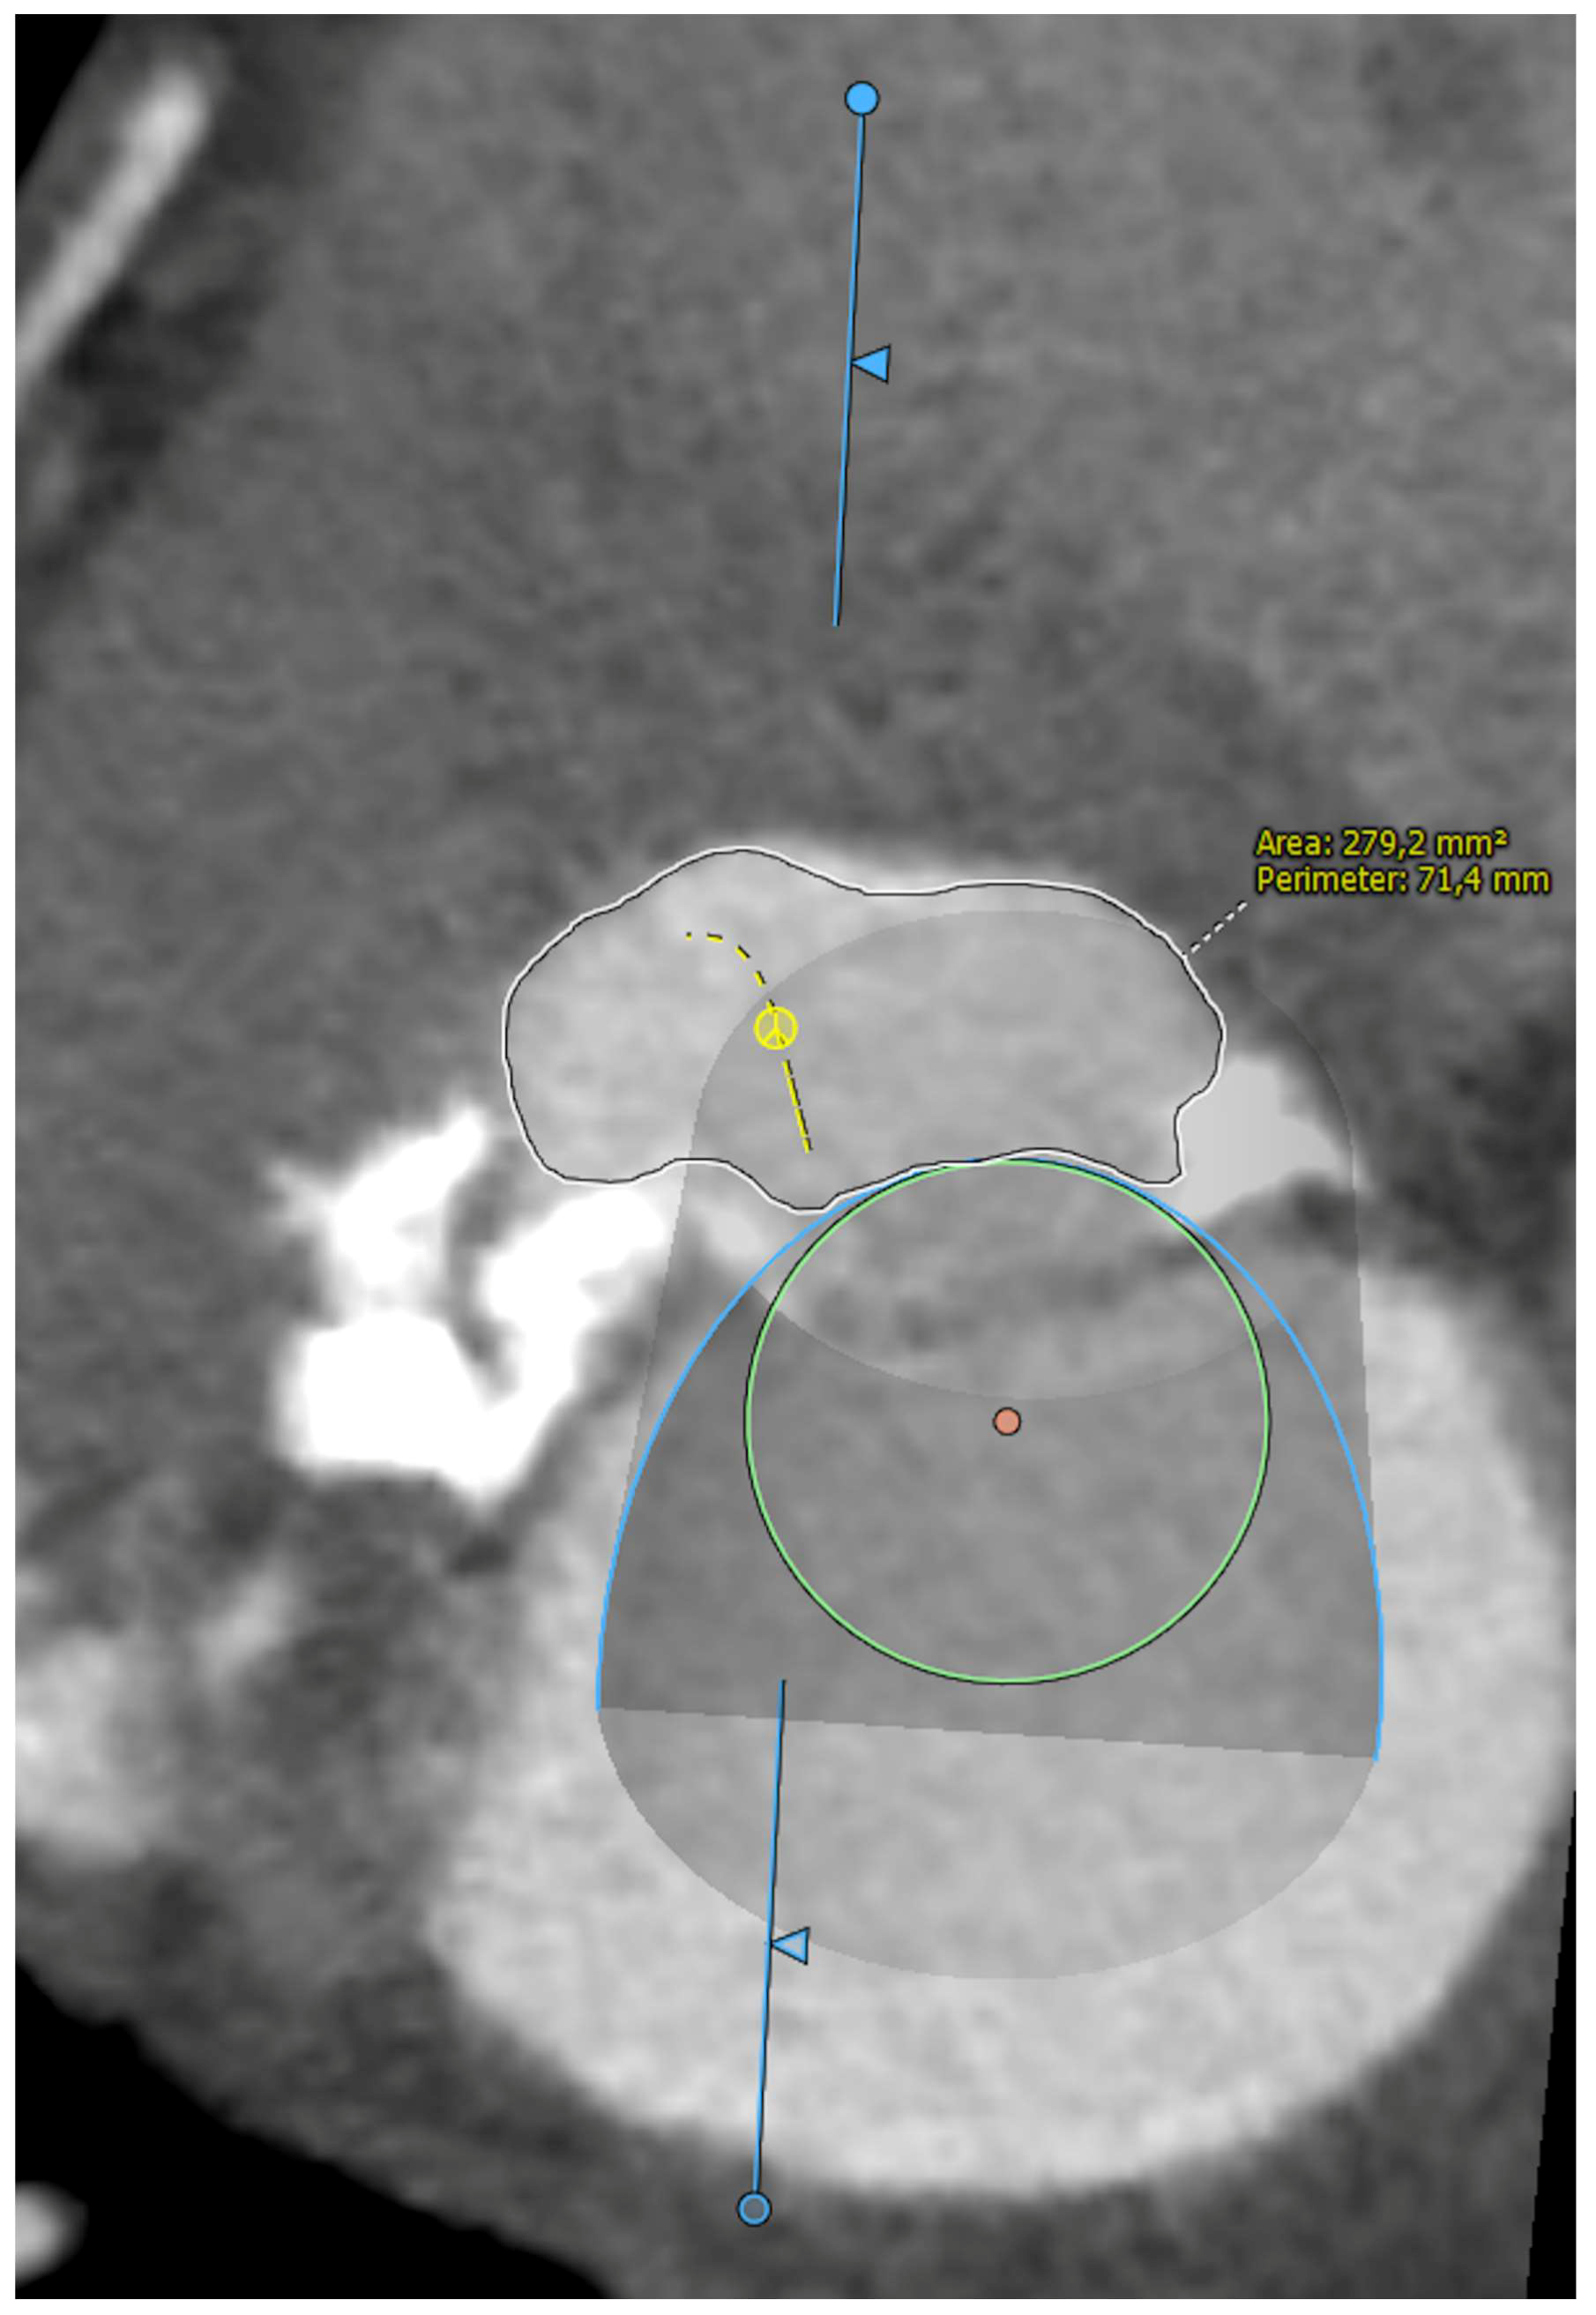

Five observational studies have been published since 2017 exploring the safety and efficacy of ViMAC, all of them with aortic balloon-expandable bioprosthesis in prohibitive surgical risk patients [17,18,19,20,21]. Their designs and main results are summarized in Table 1. To note, the ViMAC procedure shows worse results in terms of technical success and short- and mid-term outcomes than those of ViV and ViR. Indeed, ViMAC is the most challenging percutaneous scenario of all types of TMVR. Mortality at the one-year follow-up is high (around 50%), underscoring the importance of patient selection and of performing these interventions in experienced centers. When comparing the three approaches of TMVR for ViMAC, transatrial appears to have the best results, with one-year rates of mortality at 35% (25% in the latest series) [16,22,23], compared to those of transapical (57%) and transseptal (63%), and higher technical success rates (89% vs. 71% and 65%, respectively). The most important adverse event is the obstruction of the LVOT, with a hazard ratio for mortality of 2.87 (95% confidence interval 1.66–4.96) [19], so this must always be anticipated by a preprocedural CT. An area below 170 mm2 in the LVOT once the valve is implanted (“neo-LVOT”) is highly predictive of this complication (Figure 6) [13]. Other important CT parameters include the angle between the aorta and the LV axis (Figure 7), mitral annulus dimensions (Figure 8), and 2D- or 3D-derived virtual reconstructions (Figure 6).

Figure 6.

“Virtual” valve reconstruction (blue line) and neo-left ventricular outflow tract measurements.